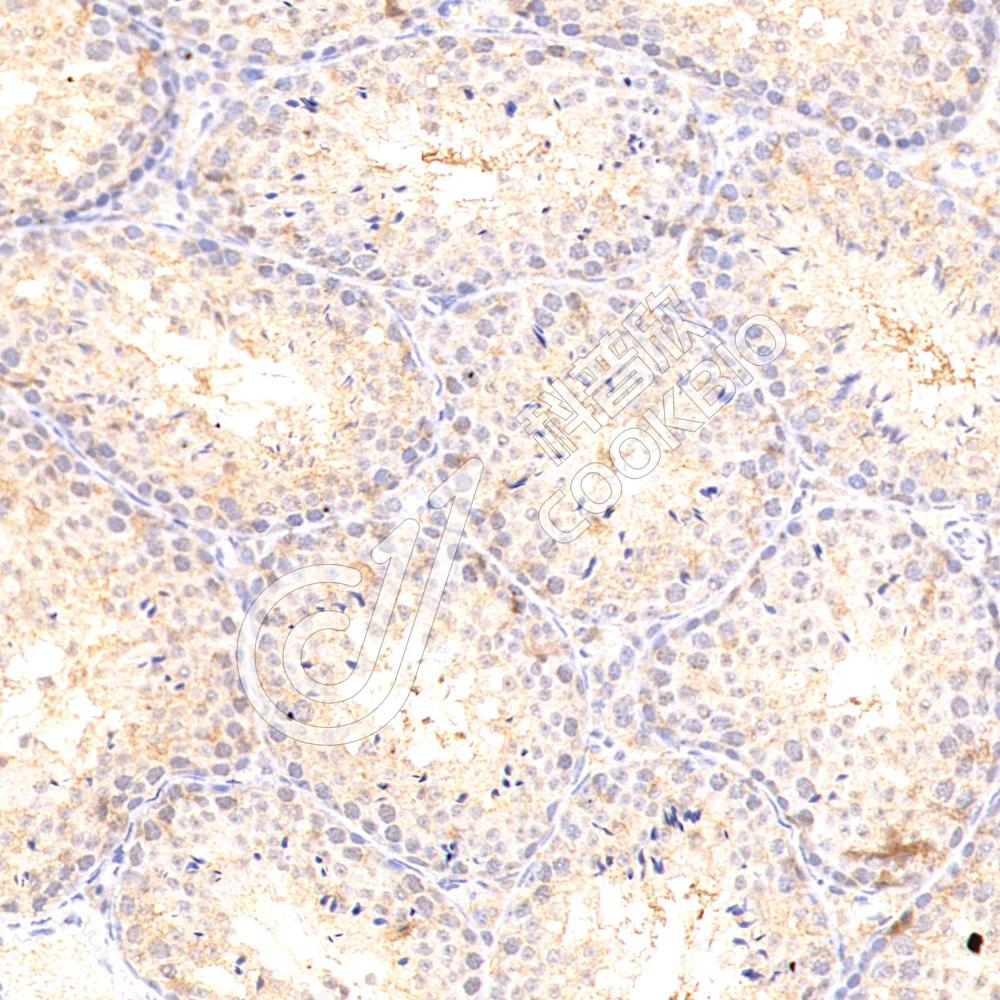

IHC检测p21蛋白(货号 K545459).

样品: 大鼠睾丸, 4%多聚甲醛 (货号KSG1101) 固定12-24小时.

抗原修复: 柠檬酸抗原修复液(干粉, pH 6.0) (KSG1201), 高压锅均匀喷气计时2分钟.

—抗: 1: 800稀释, 4℃ 孵育过夜.

二抗: S-vision免疫组化多聚二抗(山羊抗小鼠), 即用型(货号KB3903), 室温孵育20分钟.